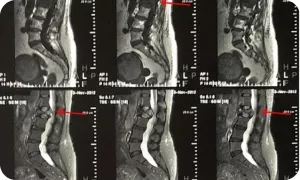

Магнитно-резонансная томография (МРТ)

Имеет клиническое значение для пациентов с переломами позвонков и компрессией спинного мозга, подозрением на наличие метастазов в головной мозг. Однако, многочисленные противопоказания к проведению МРТ требуют их первоочередного исключения у каждого, планируемого на МРТ пациента. Диагностические возможности МРТ в оценке костно-деструктивных изменений, в большинстве случаев, уступают КТ и ПЭТ/КТ.

Image

МРТ